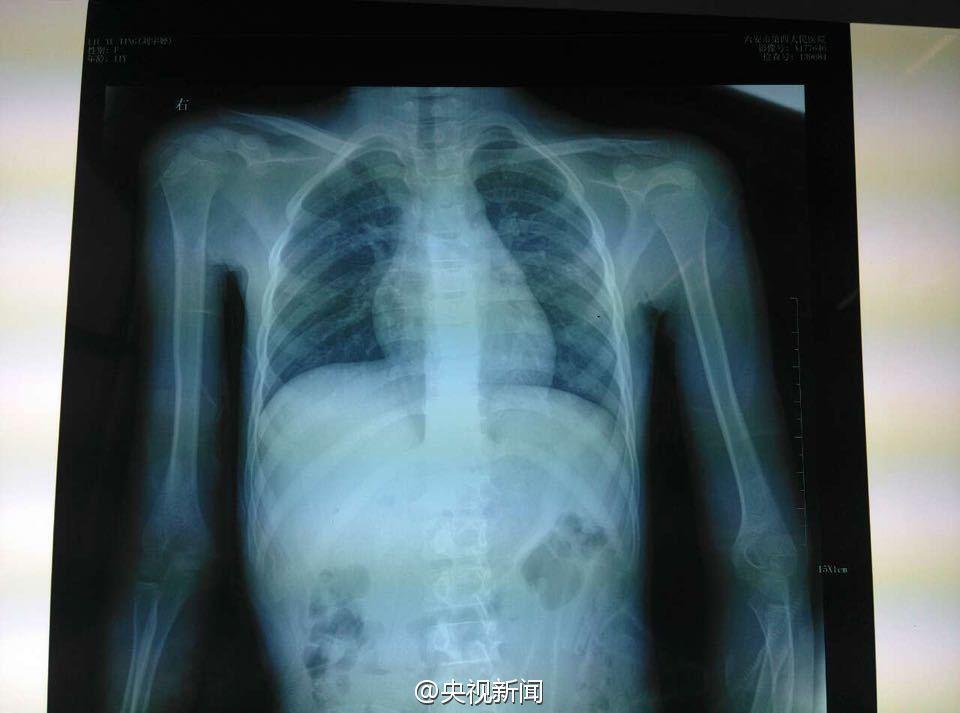

安徽11岁女孩遭母亲毒打 腿脚淤青肿胀

女孩在医院做CT检查